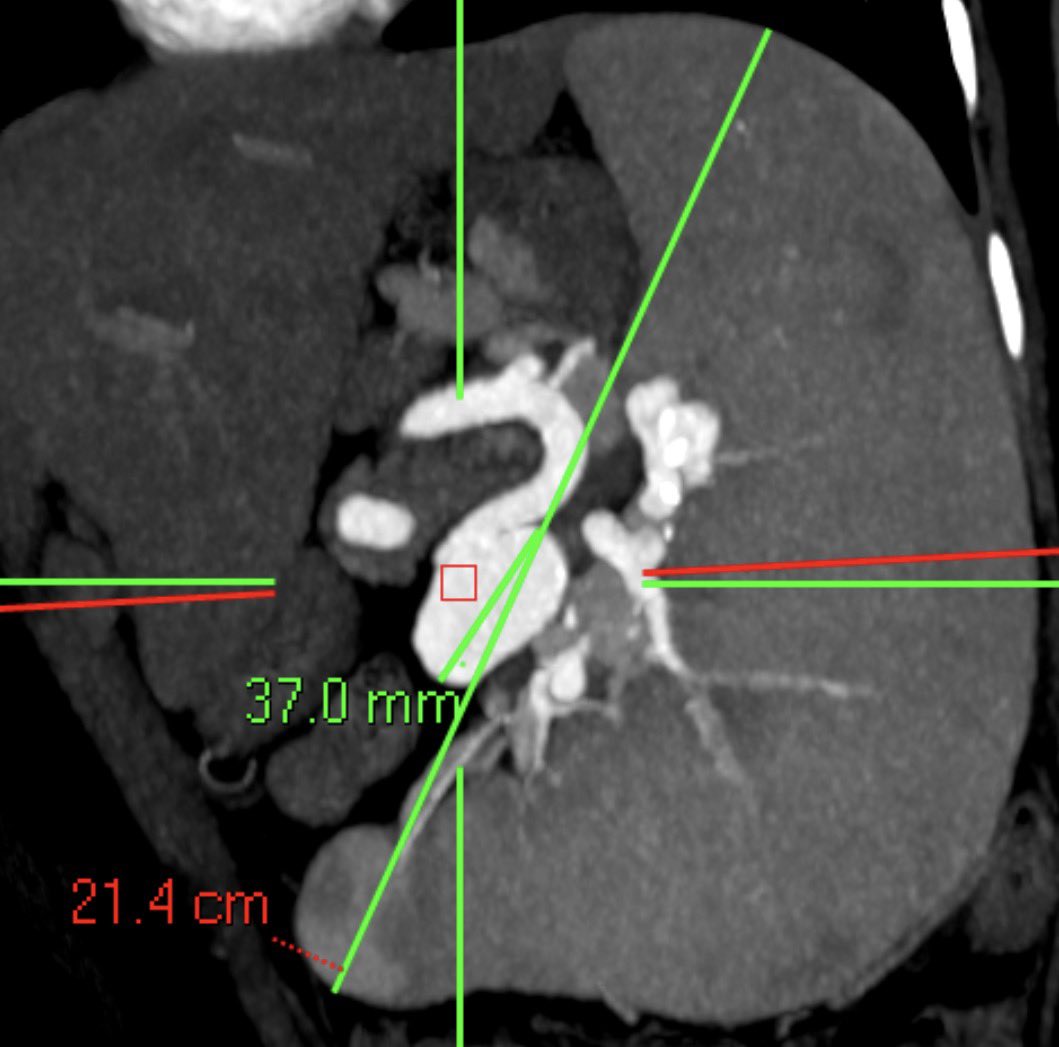

No limits in IR for developing &implementing new tech. Giant 37mm splenic aneurysm, 21+cm spleen +PH+ectatic artery: flow diver/coil embo @BSIR_News @TraineesBSIR @cirsesociety @imperialIR #vascularIR